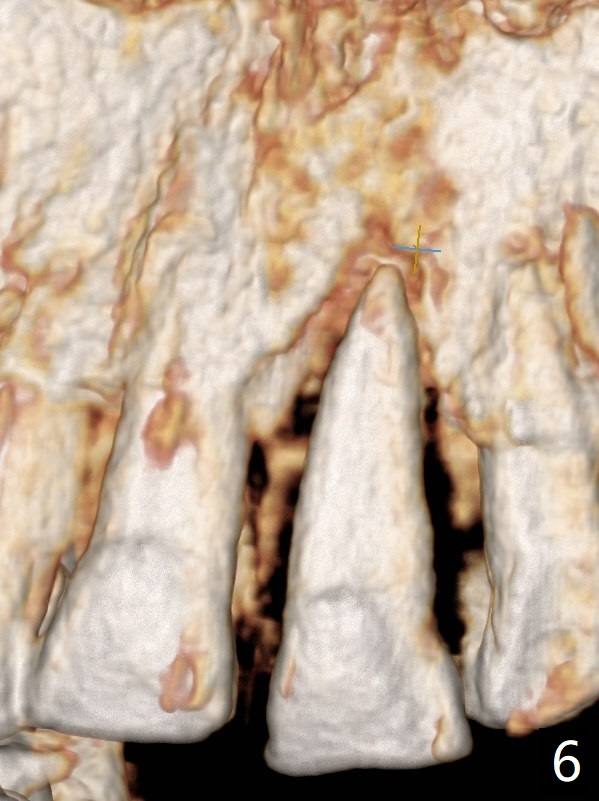

A 67-year-old man requests extraction of the loose tooth #9 (Fig.1). After extraction, the labial plate is found to be missing. With incision, allograft is kept in place with a 12x24 mm anterior narrow Cytoplast and 4-0 Chromic gut suture (Fig.2). Periodontal dressing dislodges in 2 days. The wound dehisces transversely 5 days postop (Fig.3 arrows), whereas the wound was open buccopalatal when the sutures were placed. Probably due to extensive dissection, the erythematous mucosa is large (Fig.4), although asymptomatic. When X-ray shows V-shaped bony defect (Fig.1 (PA), 5 (Pan), 6 (CT)), do not dissect the overlying thin buccal gingiva, which is most likely to dehisce. In fact immediate implant with guide appears to be more conservative, since there is no pressure against the buccal gingiva (Fig.7,8). To be more ideally, the implant could be placed more coronally, longer (13 mm instead of 11.5, Fig.9,10) and narrower (3.5 mm instead of 4.0 mm, Fig.11 (red circles: bone graft)).